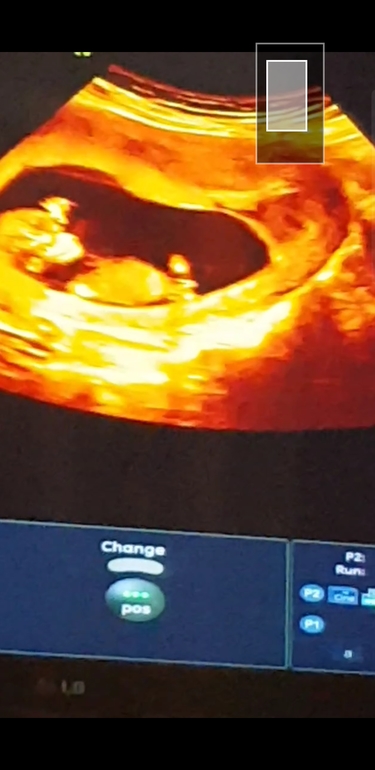

Мальчик или девочка. Первый скрининг

А вы как думаете, мальчик это или девочка. В ЖК ничего про пол не сказали

Ничего не сказали, видимо, потому что поймать ракурс нужный не смогли или не захотели. От правильного ракурса зависит многое, мальчики «превращаются» в девочек и наоборот. По этому фото ничего не скажешь. Можно предположить девочку по внешнему виду головы и строению лица. У мальчиков более угловатые челюсти чаще, но не факт опять же)

Где вы увидели признаки мальчика ??? У меня после первого скрининга все говорили что мальчик , только по внешнему виду, а ничего подобного , уже на 14 неделе мне сказали что девочка , в платной клинике, и последующие узи тоже ))) а первое фото у меня практически такое же ... фото первого скрининга 12 недель

У вас такое хорошее качество узи))) у вас тут не видно пола именно по этой фотографии. У автора открато причинное место, но пол у автора тоже сложно определить.

Особо никогда не разбиралась по фото на Узи , но очень похож на мальчика 👶🏻